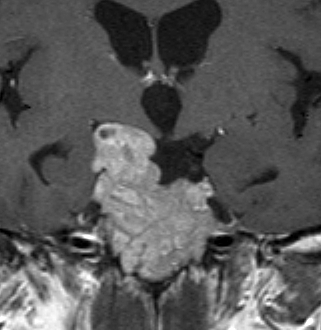

典型的なMRIの画像です

下垂体腺腫のMRIです。両側の視野障害(両耳側半盲)のために手術を受けた患者さんのものです。この腫瘍は非機能性腺腫といってホルモンを出さない腫瘍でした。少し大きめでしたが全部取れて視野の障害はよくなりました。

左の2枚はガドリニウム造影剤を使って写したもので腫瘍の形がよくわかります。右の1枚はT2強調画像と言います。MRIでは撮影の仕方によって見え方が違います。